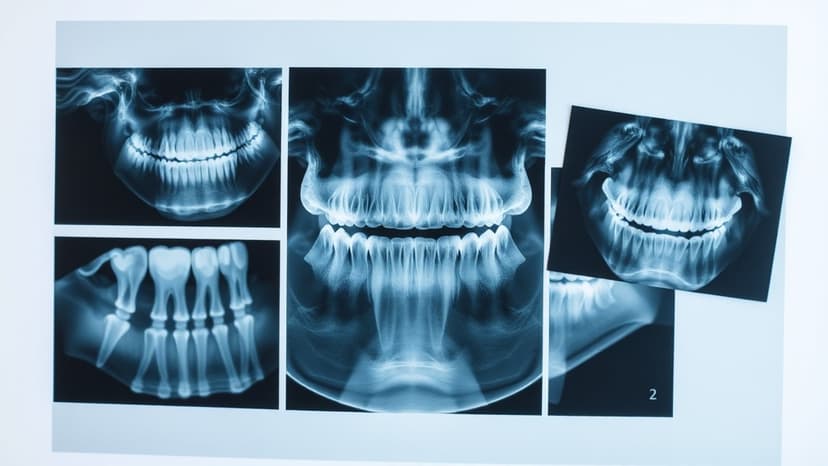

Starting next April, the UK government plans to offer dentists increased payments for emergency and complex treatments to improve patient access to NHS dental care in England. This initiative aims to combat the growing problem of 'dental deserts' and 'DIY dentistry' resulting from many dentists ceasing NHS work due to unrecouped costs for procedures.

Despite the government's claims of modernizing NHS dentistry and preventing avoidable hospital admissions, significant skepticism persists. The British Dental Association asserts the proposed changes lack new funding, while health watchdogs question their effectiveness in addressing the ongoing crisis and delivering on targets for urgent dental appointments.

The proposed contract changes, which include a standardized payment package for complex care that could save patients approximately £225, are described by critics as mere 'tweaks' to a failed system. Experts emphasize the need for fundamental reform and transparent reporting to restore public confidence in NHS dentistry.